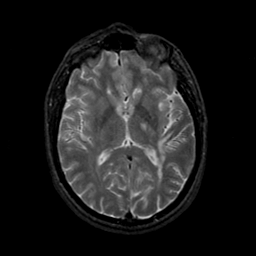

MR Study #23, January 26, 1992 -- Slice #26